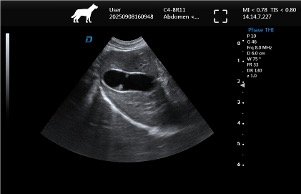

| Imaging Quality | Clear 2D, stable grayscale, optional Color Doppler for abdominal, cardiac, reproductive exams | Ensure system covers most frequent clinical exams |

Common Clinical Applications

▸ Abdominal examinations (liver, kidneys, bladder, spleen)

▸ Pregnancy diagnosis & reproductive monitoring

▸ FAST & emergency ultrasound assessments

▸ Basic cardiac screening

▸ Routine follow-up & monitoring